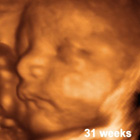

بنات الله يعافيكم انا كان في خاطري أصلح مستقبلا ان شاء الله سونار رباعي لكن حقيقة شفت هنا بالنت صور لسونار رباعي وأشكالهم حقيقة تفجع وأبد مو حلوة استغفر الله

فهل هو فعلا يطلع لونهم وشكلهم كذا في السونار الرباعي يالي جربتوه ؟

يعني يوم شفتي الصورة مثل ما تأملتي ولا خفتي ؟

انا كنت احسب انه يكون واضح زي الطبيعة حتى قريت مرة هنا لوحدة تقول بنتي شعرها كثير شفته بالسونار الرباعي طيب كل الصور الي شفتهم بالنت صلع مو مبين ولا شعرة وحدة حتى يعني هو صدق كذا ولا كيف يا جماعة ..

ماحسيته يبين الشبة

نفس اللي بالنت مو مثل مايقولون البنات بالوان

هو اللون برتقالي مدري اصفر

بتطلع الصور بهالطريقة

و بالعكس حلو.. بتحسي بالترابط مع البيبي يلي ببطنك

بس ما يبين لا شعر و لا ملامح

بس تتطمن الدكتورة على نمو الأعضاء و تشكل الوجه كاملاً